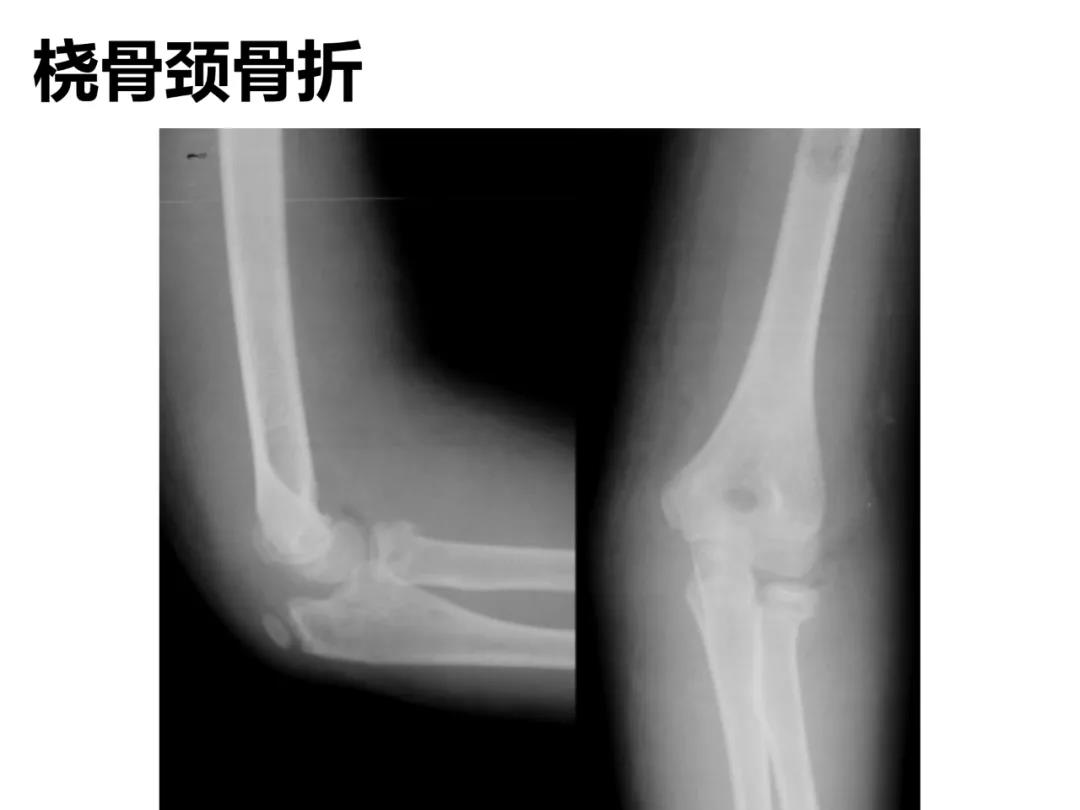

小儿骨科X线片汇总,临床读片宝典!